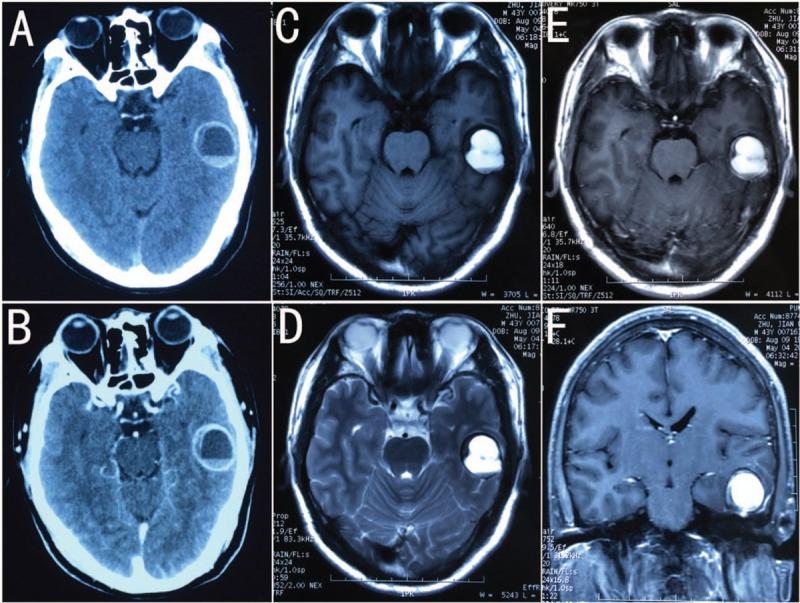

A 43-year-old man presented with headache and memory deterioration. Brain computed tomography and magnetic resonance imaging showed a slightly enhanced temporal lobe cystic lesion, which was homogenously hyperintense on T1-and T2-weighted images. There was a suspicion of brain abscess at admission. The lesion was totally removed with a left subtemporal craniotomy. Histological examination revealed an EC with intracystic hemorrhage.

一名43岁男性因头痛和记忆力减退就诊。脑部计算机断层扫描和磁共振成像显示颞叶有一个轻度强化的囊性病变,在T1加权和T2加权图像上呈均匀高信号。入院时怀疑为脑脓肿。通过左颞下入路开颅手术将病变完全切除。组织学检查显示为伴有囊内出血的EC。